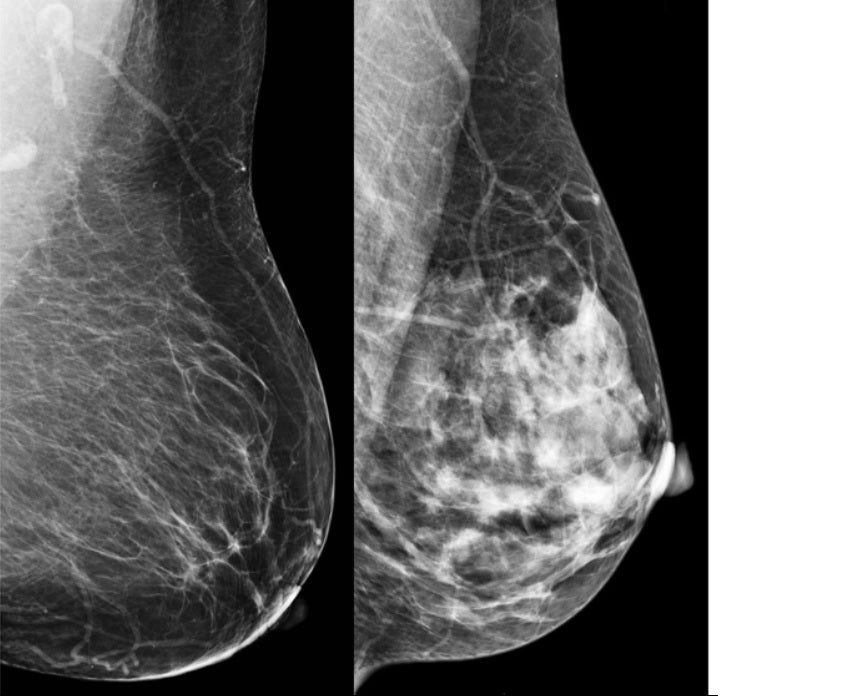

Una mama predominantemente grasa (izquierda) frente a una mama muy densa (derecha). En la mama densa, el tejido glandular aparece blanco igual que un posible tumor, pudiendo ocultarlo y dificultar su detección. En estos casos la ecografía ayuda a ver el tumor que la mamografía podría no diagnosticar.

Por otro lado, la ecografía tiene sus propias virtudes. Las mamografías producen una imagen bidimensional donde el tejido glandular de la mama se ve blanco. El problema, es que los tumores ¡también se ven blancos en mamografía! Esta coincidencia entre el tejido glandular normal y los tumores puede ocultar lesiones en mamas muy densas. Así, en mujeres jóvenes o con senos densos, un pequeño cáncer puede «camuflarse» en la mamografía y pasar desapercibido. La ecografía nos ayuda al permitir ver a través de la densidad mamaria y distinguir lesiones ocultas en mamografía. Son un equipo: la mamografía y la ecografía se complementan y no se puede sustituir una por otra. De hecho, estudios muestran que, por cada 1000 mujeres examinadas, la mamografía de cribado detecta aproximadamente 4 a 6 cánceres, y si se añade una ecografía mamaria en mujeres de mama densa, se pueden encontrar 2 o 3 cánceres adicionales. Gracias a esta complementariedad, «no se nos escapa ningún cáncer», tal como señalaba Fuen en el vídeo: cada prueba ve aquello que la otra puede pasar por alto. Ambas técnicas se apoyan mutuamente para lograr la mejor detección del cáncer de mama.